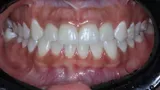

Guided rehabilitation with implant in upper incisors region, after loss due to root resorption

In the following pages, you will find some of the landmark cases that have shaped Neodent history so far.

Learn more about the Neodent implants and abutments versatility, and how our solutions meet from single-units to full-arch restorations, conventional and digital workflow, and anterior and posterior cases.